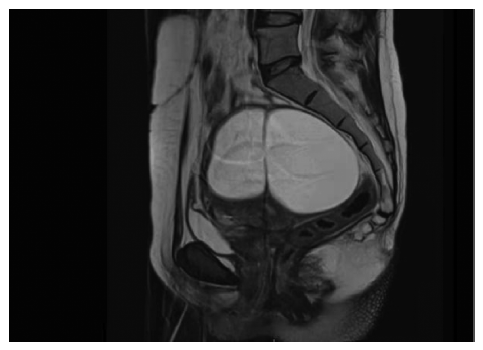

入院查体:盆腔内触及直径约11 cm囊性包块,张力大,活动好,无压痛,与子宫及双侧附件分界不清。2020年11月19日查肿瘤标志物示:糖类抗原72-4(carbohydrate antigen 72-4,CA72-4)为46.52 U/mL,CA125、CA19-9、甲胎蛋白(alpha fetoprotein,AFP)、癌胚抗原(carcinoembryonic antigen,CEA)及人附睾蛋白4(human epididymis protein 4,HE4)均未见异常。2020年11月21日盆腔磁共振成像(magnetic resonance imaging,MRI)示(见图2):子宫右前壁膨隆,见囊状异常信号肿块影,大小约11.1 cm×6.3 cm×6.1 cm,考虑子宫肌瘤囊性变。初步诊断:盆腔肿物(子宫肌瘤囊性变?)。2020年11月24日行剖腹探查术,术中见:子宫不规则增大如妊娠3个月,前壁及宫底均呈囊性凸起,囊壁薄,双附件未见异常。按照患者及其家属术前意愿行全子宫+双侧输卵管切除术。术毕剖视子宫见子宫前壁及宫底2个囊腔,囊液清亮淡黄色,囊壁光滑,囊腔周围子宫肌层组织少(见图3和图4)。术后病理示:(子宫)符合间皮囊肿,2个囊腔大小分别为3.5 cm×3 cm×2 cm和4 cm×3 cm×2.5 cm。免疫组织化学染色提示(子宫)囊壁被覆上皮:GATA3阴性,配对盒基因8(pair box-8,Pax-8)阳性,肾母细胞瘤基因1(Wilm′s tumour gene-1,WT-1)阳性,间皮细胞阳性,D2-40阳性,CD31阴性,天冬氨酸肽酶A(Napsin A)阴性,结合苏木精-伊红(Hematoxylin-Eosin,HE)染色切片(见图5),本病例诊断为子宫间皮囊肿。患者术后恢复好,随访至2021年11月无异常。

图2

子宫间皮囊肿的术前诊断较为困难,因患者常无特异性的临床表现,多数以盆腹腔包块首诊,仅少数患者有月经过多的临床表现,影像学及实验室检查亦缺乏特异性,术前易误诊为子宫肌瘤囊性变、卵巢囊肿、盆腹腔炎性包裹性积液和盆腔囊性淋巴瘤等。本例患者亦无典型临床表现,术前误诊为肌瘤囊性变,回顾性分析术前影像资料,B超示子宫右前壁囊性暗区,囊内见细密点絮状回声,内见分隔。MRI示肌壁间囊性包块内部信号均匀,T1加权成像(T1 weighted imaging,T1WI)呈低信号,T2加权成像(T2 weighted imaging,T2WI)呈高信号,弥散加权成像未受限,囊壁菲薄、增强扫描囊壁及分隔明显强化,强化程度与肌层相当。首先通过影像学明确囊肿位置位于子宫体而非卵巢,彩色多普勒超声未提示囊壁上丰富血流信号,MRI提示囊壁强化与肌层相当,则提示良性病变可能性较大。子宫肌瘤囊性变因变性部分为液体,超声图像上常表现大小不等的无回声区,或相互融合为较大的囊腔。而其在MRI中T1WI呈低信号,T2WI呈高信号,与子宫间皮囊肿难以鉴别,但子宫肌瘤囊性变通常囊壁较厚[10-11],而子宫间皮囊肿囊壁菲薄。因妇科及影像学医师缺乏对子宫间皮囊肿的认识,本例患者术前误诊为子宫肌瘤囊性变。因此影像学和妇科医师应加强对该病的了解,对术前明确诊断具有重要意义。